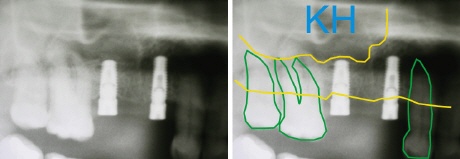

Nach fünf Monaten sind die Implantate im Knochen eingeheilt und auch der aufgebaute Knochen ist mit dem umliegenden Knochen fest verwachsen. Die beiden gelben Linien zeigen den festen (der Implantologe spricht von konsolidierten) Knochen zwischen den Implantaten.

Die Implantate können nun mit Kronen versorgt werden.